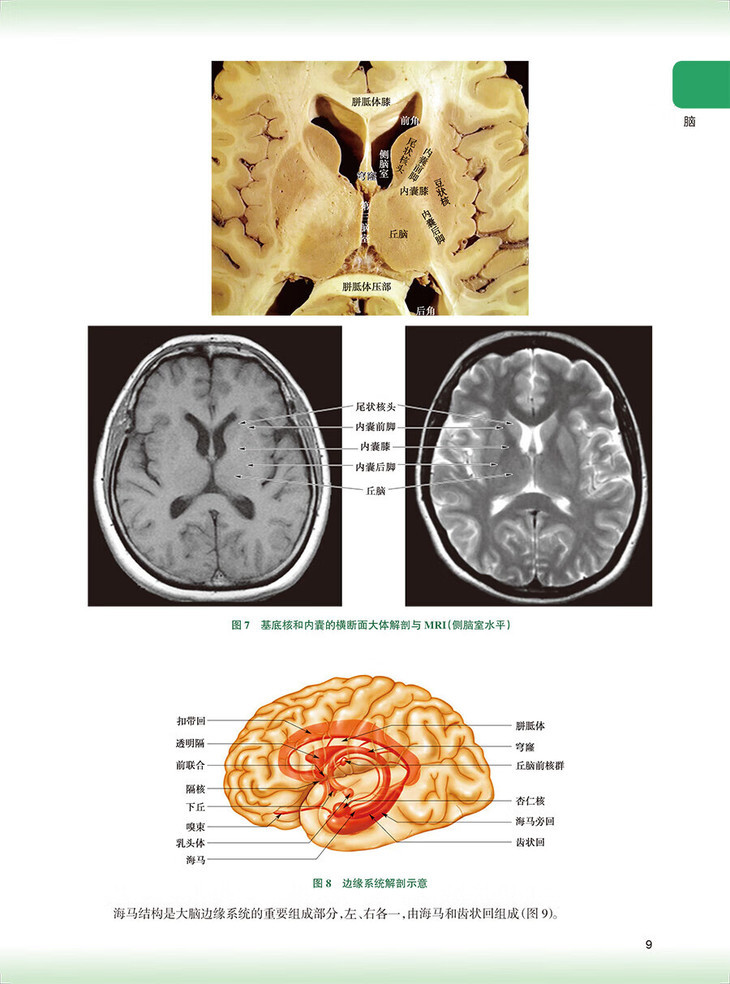

脑/1